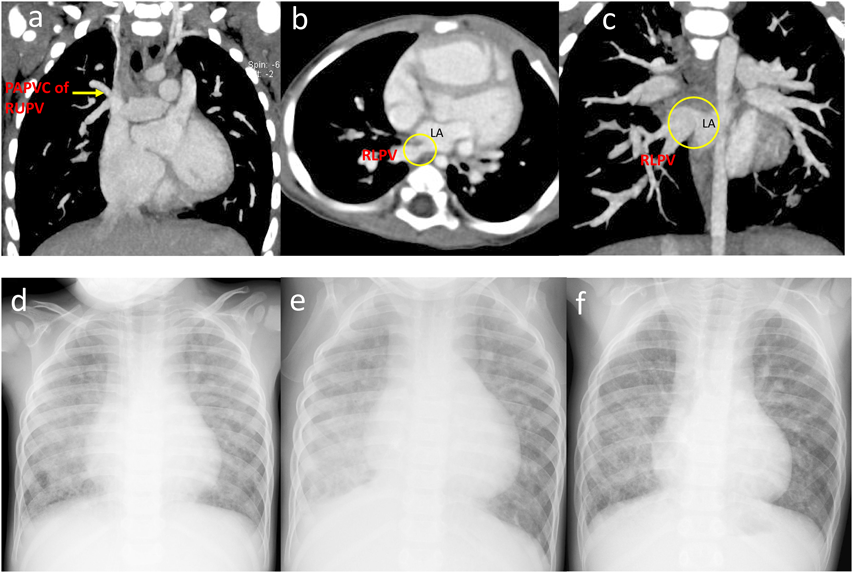

Fig. 1 a) CT at 8 months showing a partial anomalous pulmonary venous connection of the right upper pulmonary vein. b, c) CT at 8 months showing stenosis of the ostium of the right inferior pulmonary vein into the left atrium. d) Preoperative chest radiography. Diffuse congestion can be seen in both lungs, with severe congestion particularly evident in the right lung. e) Postoperative chest radiography showing the accumulation of pleural fluid in the right lung. f) Chest radiography 2 years after surgery. Most of the pleural fluid had been absorbed, and the upper and middle lobes of the lung had increased in size to compensate for the resected portion.

The patient was a boy aged 3 years and 5 months. He was born via a cesarean section at 39 weeks’ gestation, with a birth weight of 2,354 g. He had no family history of congenital heart disease. At 2 months of age, he was diagnosed congestive heart failure with atrial septal defect when he suffered from viral infection. At 6 months, he was referred to our institution for further examination and treatment. Three-dimensional computed tomography (CT) revealed the right superior partial anomalous pulmonary venous connection to the superior vena cava and the stenosis of the right inferior pulmonary vein at the orifice (Fig. 1a–c). No stenosis was observed in the left superior pulmonary vein. At 9 months, cardiac catheterization revealed that he had an elevated mean pulmonary arterial pressure (28 mmHg) with a normal pulmonary artery wedge pressure bilaterally (10 mmHg). His left inferior pulmonary vein drained into the left atrium via the left superior pulmonary vein. The pulmonary to systemic flow ratio (Qp/Qs) was high, at 3.7, indicating that PH was due to increased pulmonary blood flow by atrial septal defect (Table 1).

Despite the improvement of PH, he suffered from focal right lower lobe pneumonia complicated with pulmonary hemorrhage repeatedly from the age of 2 years and 4 months. At 3 years and 5 months of age, we performed further examinations including cardiac catheterization. On chest X-ray, there was diffuse pulmonary congestion in both lung fields without pleural effusion (Fig. 1d). The ejection fraction was 63%, and the ratio of right-to-left ventricular systolic blood pressure was estimated to be 0.52 by echocardiography. The blood flow velocity was 2.1 m/s in the right pulmonary veins indicating the remaining of right PVS. On cardiac catheterization showed the descending aortic pressure and the pulmonary arterial pressure was 70/44 (55) mmHg and 42/17 (29) mmHg, respectively. The pulmonary vascular resistances calculated using pulmonary blood flow ratio (right : left=3 : 97) by lung perfusion scintigraphy were 38.9 units m2 on the right and 3.60 units m2 on the left (Table 1), indicating that the pulmonary vascular resistance was improved by medical intervention. Right pulmonary arteriography revealed diminished pulmonary vascular bed, right lower PV obstruction (Movie).

Movie 1

These results showed the patient’s ventilation and blood flow were primarily dependent on the left lung. Bronchoscopy did not reveal the bleeding point in the right main bronchus. The recurrent infection and hemoptysis in the lower lobe of the right lung were considered life-threatening. Therefore, we decided to perform a partial resection of the lower lobe of the right lung. The lobectomy proceeded without complication, and he was discharged 1 month after surgery. On X-ray, unlike many adult cases right upper and middle lobes increased in size to compensate for the resected portion of the right lower lobe without a mediastinal shift (Fig. 1e, f). The administration of bosentan, sildenafil were continued to treat the pulmonary arterial hypertension. Although he was subsequently re-admitted twice for pneumonia, there was no evidence of hemoptysis for 5 years following the lobectomy. Oxygen saturation is 96% on room air, and he continues oxygen therapy only during night and goes to school without exercise restrictions.